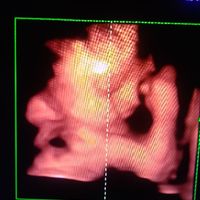

2950 giorni faCiao ragazze sono a 21+3 e oggi abbiamo fatto morfologica..... É una polpetta.... 502gr..... Siamo contentissimi